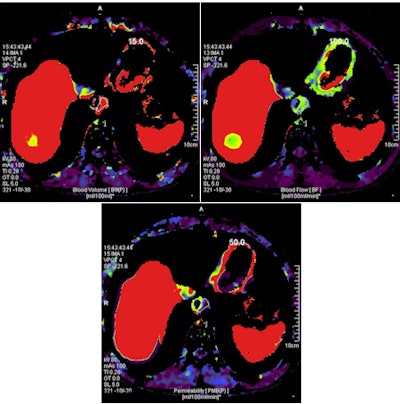

A 68-year-old man with an 8-mm distal esophageal mass with biopsy-proven squamous cell carcinoma. On coronal PET, axial PET, and axial fused PET/CT images (above), the primary tumor demonstrates no significant FDG uptake. Axial CT image shows esophageal mass at the same level. In the same patient, functional perfusion maps of blood volume, blood flow, and permeability surface (below) reveal the intratumoral perfusion distribution. CT perfusion values for blood volume (left), blood flow (right), and permeability surface (bottom) were 9.62 mL/100 mL, 86.67 mL/100 mL/min, and 12.65 mL/100 mL/min, respectively. All images courtesy of Dr. Mecit Kantarci.